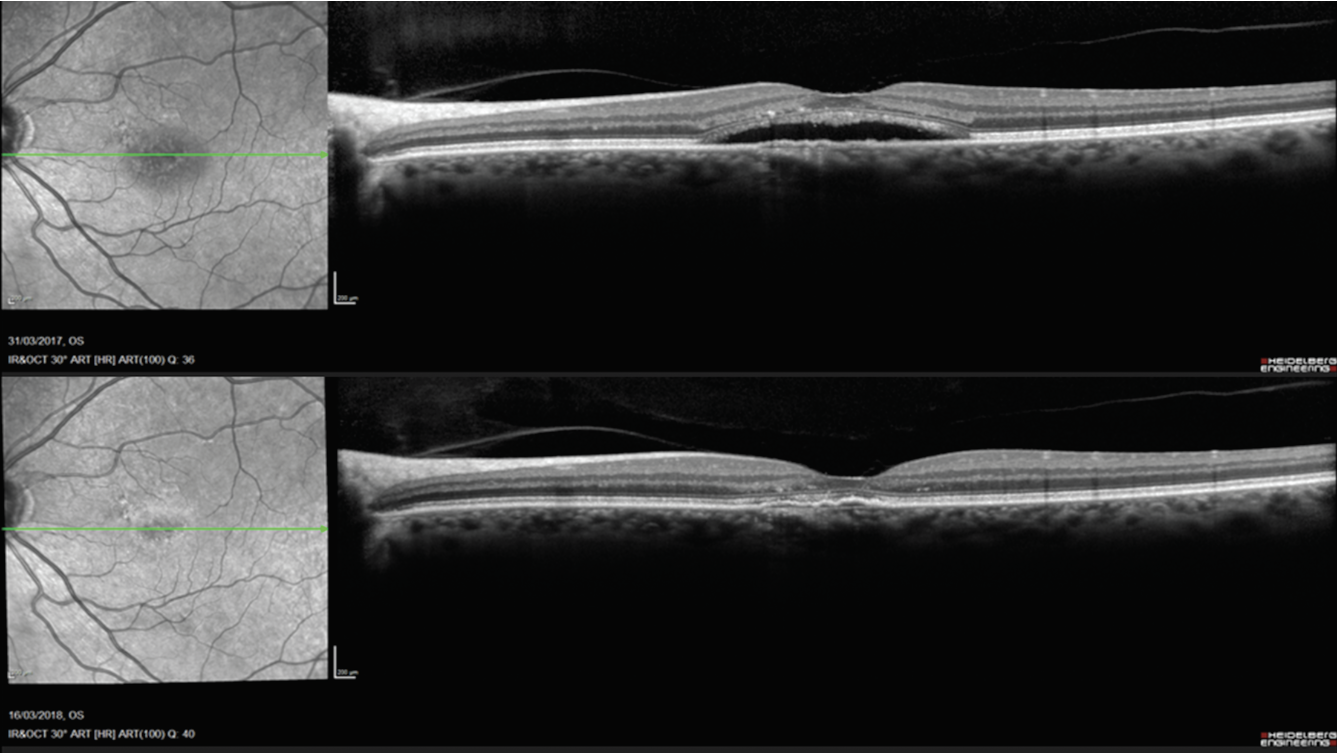

Longer-term treatment benefits have also been observed. For instance, one study reported sustained structural anatomical changes and visual acuity stability over two years following half-dose PDT in patients with chronic CSCR.5 Its findings provided further reassurance about the durability of treatment results in properly selected patients.